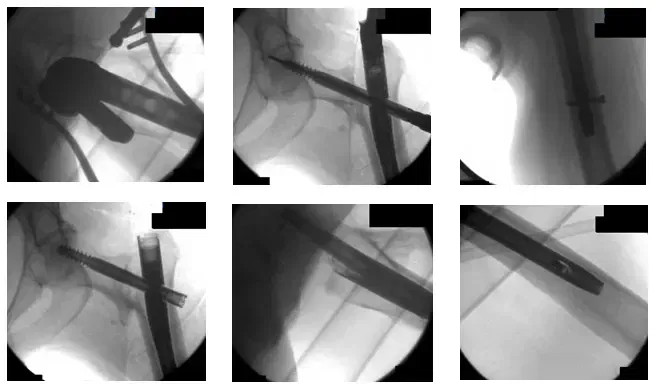

Intraoperative radiographs of the left hip show fixation of the intertrochanteric fracture using an intramedullary rod transverse of the fracture